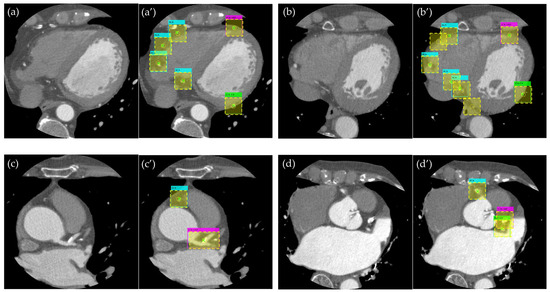

3.1. Evaluation of the Object Detection Model

3.2. Evaluation of Detection Accuracy Using Additional Metrics

4. Discussion